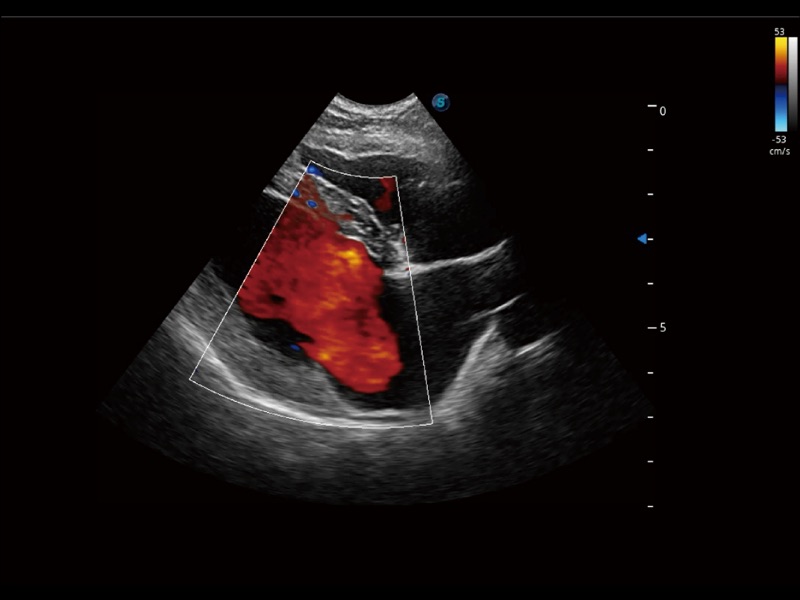

能够基于左心室壁追踪和辛普森法,自动计算射血分数,支持多个可移动点描迹,与手动测量相比,极大节省了动物医生的时间和精力。

当心脏测量结果超出正常范围时,可实时预警提示动物医生,减少疾病漏诊概率。